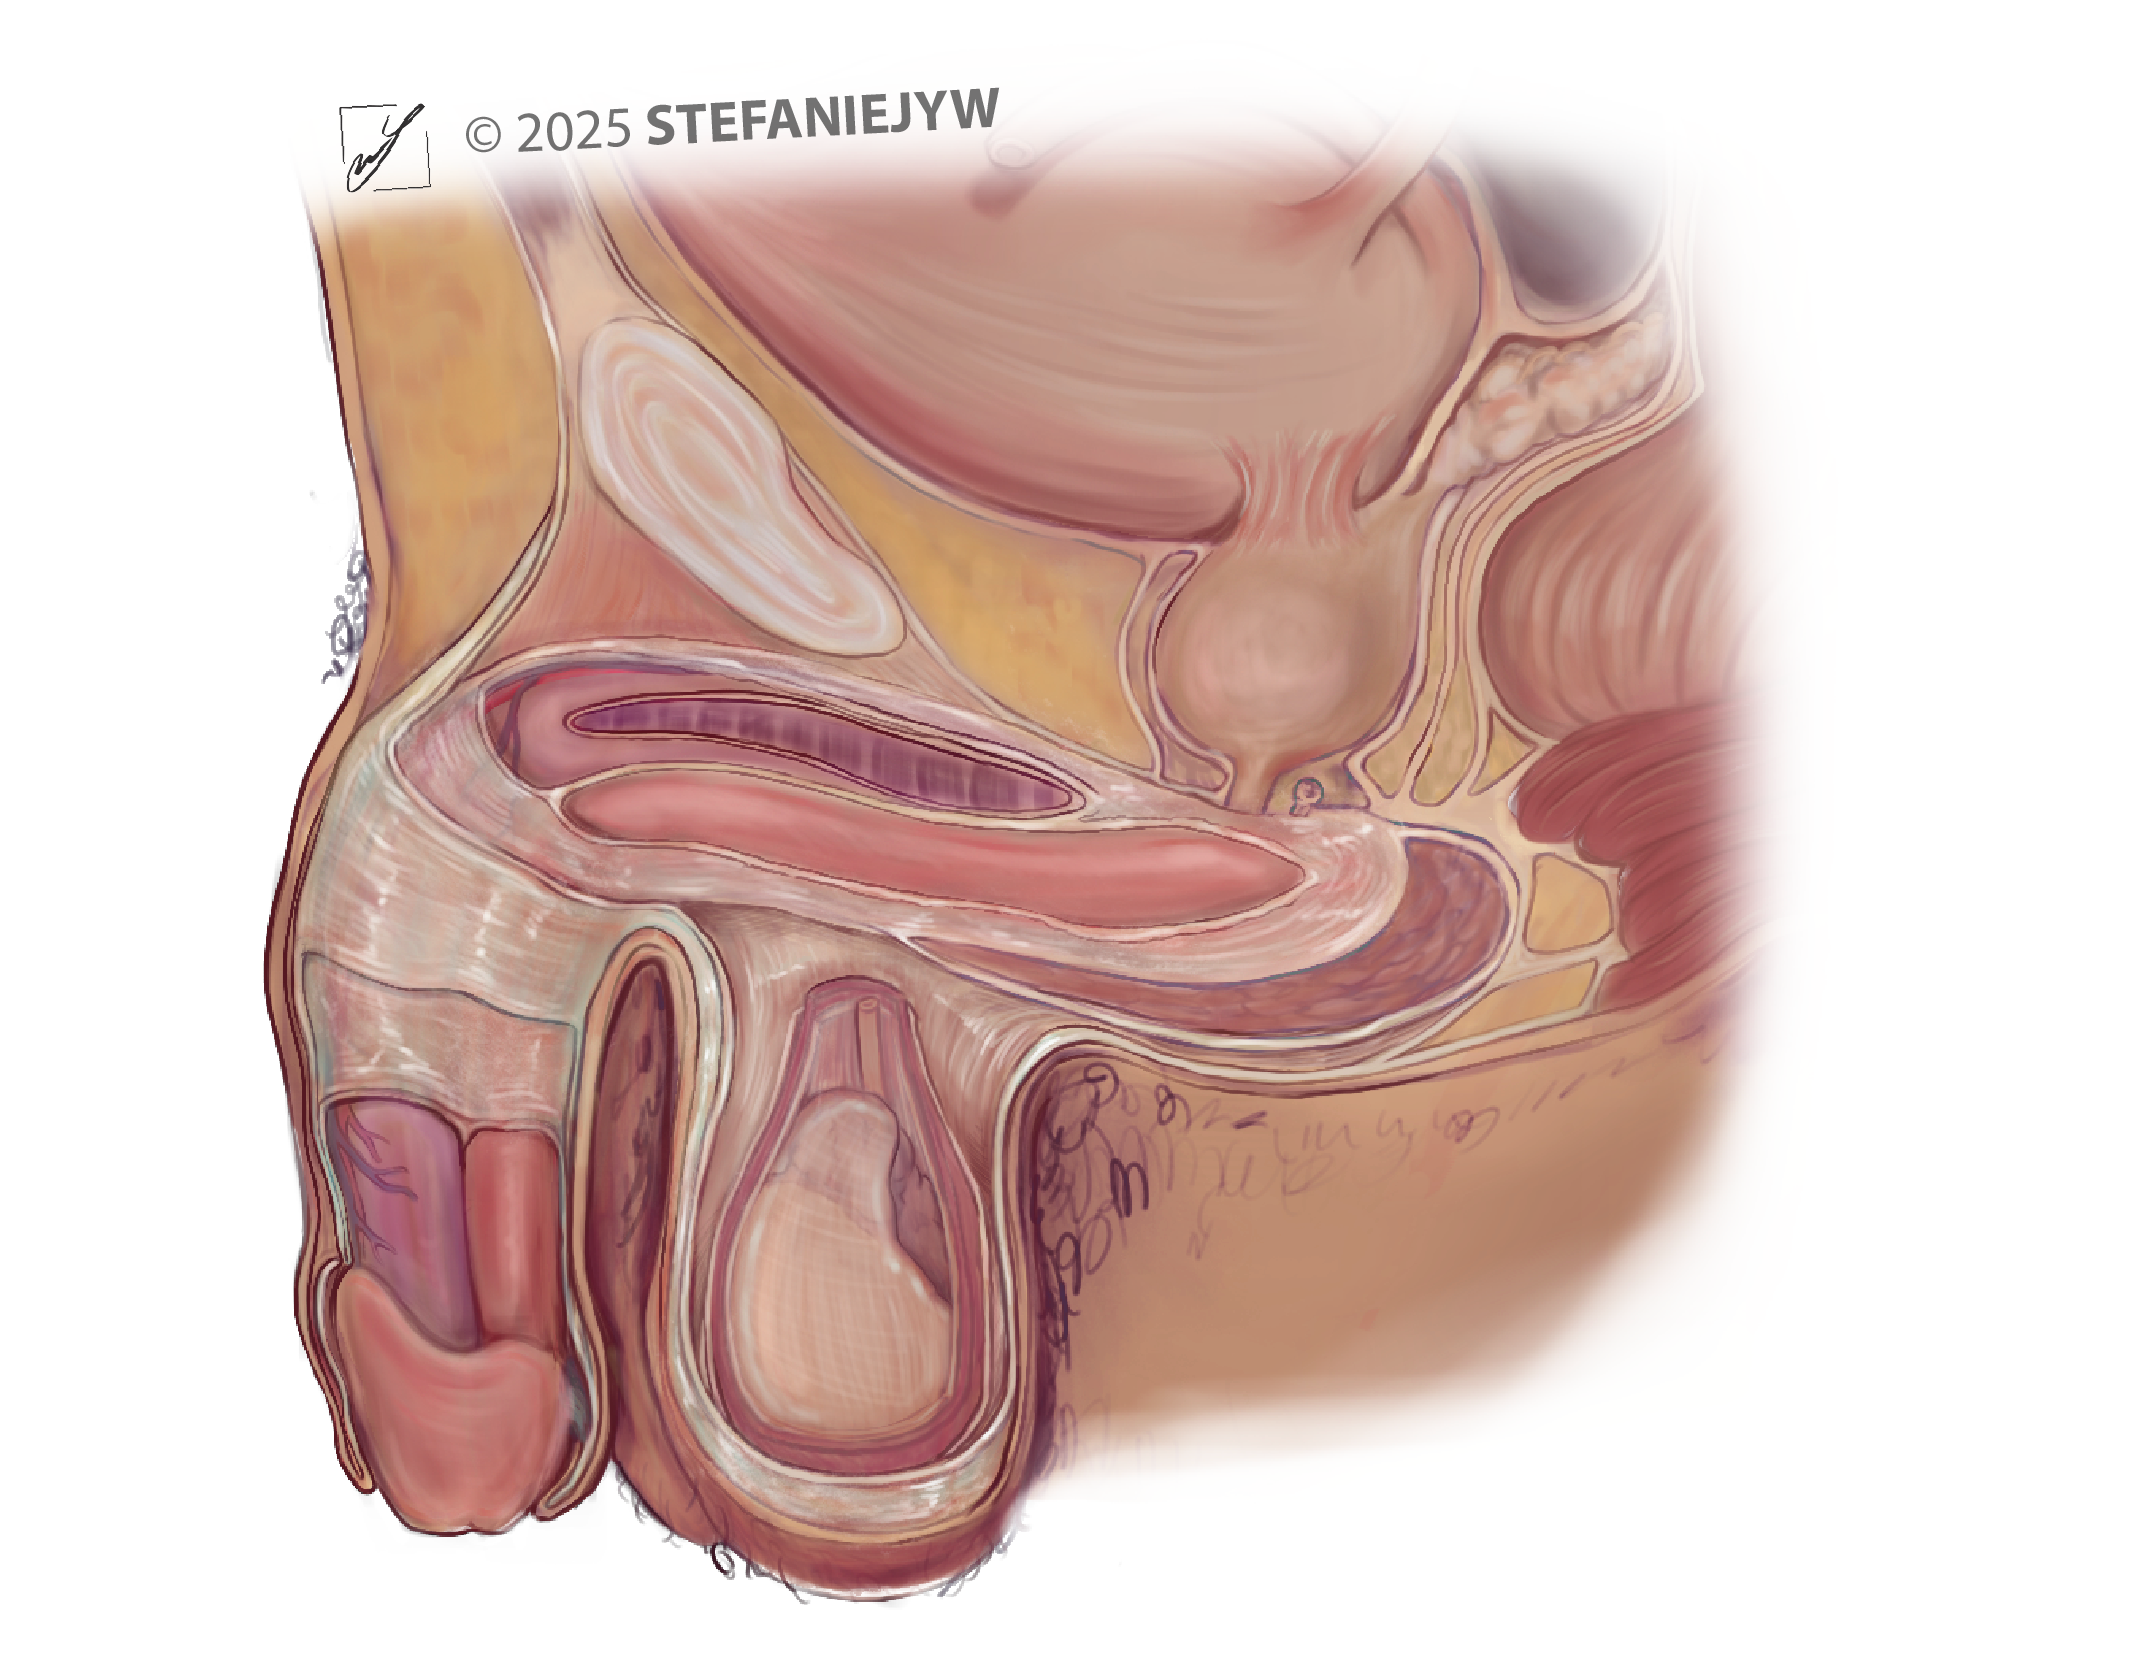

Series: Inclusive Anatomy